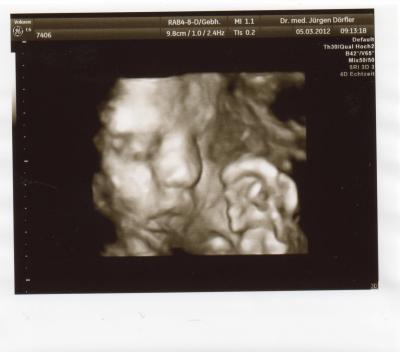

Hallo,ihr lieben hatte heute wieder VU und ich bin total verliebt Unsere Maus ist heute bei SSW 31/3 ca.42cm groß und 1700g schwer. Bild hab ich auch wieder bekommen..... LG

Bild zu Zurück vom FA - Forum für Mai - Mamis

Schön das alles in Ordnung ist und ein wunderschönes Bild hast du bekommen!

Supersüßes Bild ! Ich freu mich immer total über eure Berichte und Bilder, das verkürzt einem selbst auch etwas die Wartezeit auf den nächsten Termin.

Super suess die maus. Und dazu super werte. Lg